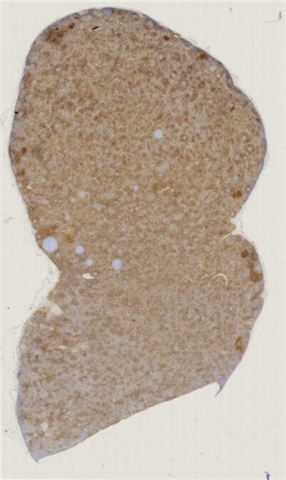

案例2 (6860)

性别:       年龄:73

患者详情: 于手术前10天无意中发现左侧大腿内侧肿物,体检肿物位于皮下,病程不详,无其他有关症状,入院后其他检查无特殊,在全麻下行肿物切除,术中肿物位于皮下

大体所见: 肿物大小3.5*3*2.5厘米

医院: 上海交通大学医学院附属新华医院崇明分院